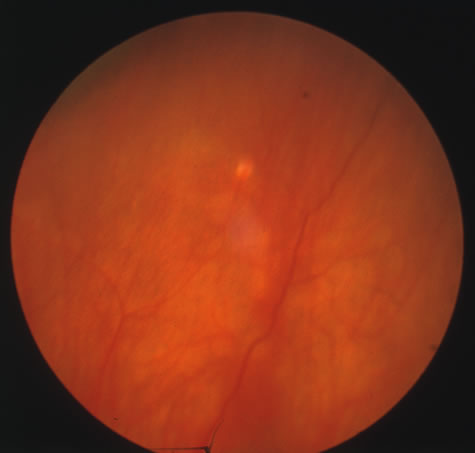

The acute retinal necrosis (ARN) syndrome is most often caused by the herpes zoster virus, although occasionally it may be a result of herpes simplex infection.12 It is typically described in healthy patients although association with immunosuppressed patients has also been described. Granular, nonhemorrhagic areas of retinal necrosis may be observed in the fundus, often rapidly coalescing with resulting blindness often caused by retinal detachment. There is often an associated vasculitis and vitritis. In immunocompromised patients VZV or HSV retinitis may also take the pattern of progressive outer retinal necrosis (PORN) (Fig. 6). PORN differs from ARN in that the former is multifocal, localized to the outer retina, and is less often associated with vasculitis and vitritis.

|